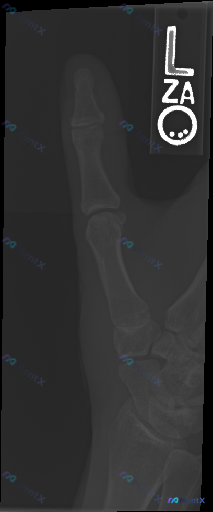

左手拇指影像未见明显骨质异常,但如果有临床症状该怎么考虑?

整理了一份左手拇指的影像资料,先不说最终结论,大家可以先看一下影像描述的核心信息:

- 投照位置:左手拇指斜位/侧斜位

- 骨皮质、骨小梁:连续完整,排列规律,密度均匀

- 关节:IP、MCP、CMC关节间隙清晰,对位良好

- 其他:无骨折脱位、无骨质破坏、无明显软组织肿胀

如果只是拿到这份影像报告,但患者可能有疼痛或活动受限的主诉,接下来的思路会往哪边靠?